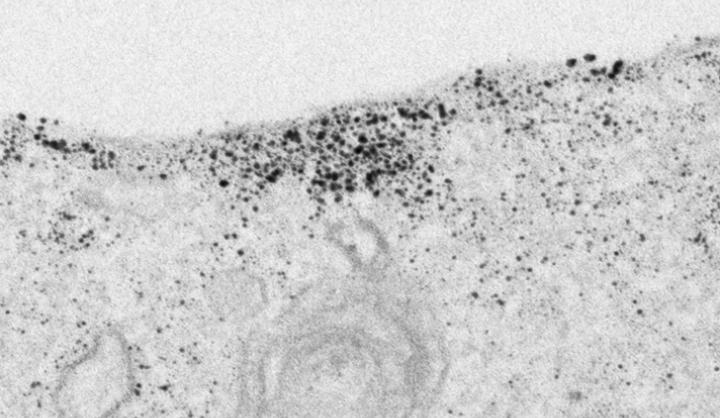

Immagine di microscopia a immunoelettrone della proteina tau accumulata sulla membrana cellulare. (Fonte: Henri Huttunen)

"Quando falliscono i meccanismi regolatori della tau, la proteina finisce nella membrana della cellula, invece che nel suo citoscheletro. Le zattere lipidiche ricche di colesterolo della membrana cellulare sembrano avere un ruolo centrale in questo meccanismo di secrezione della tau", dice Huttunen. Lo studio ha usato neuroni coltivati e proteine navetta fatte su misura per osservare da vicino il trasferimento della tau tra le cellule.